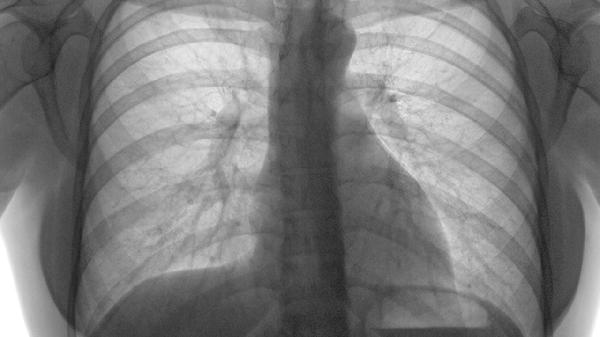

肋软骨炎可通过热敷、药物治疗、物理治疗、中医调理、手术治疗等方式改善。肋软骨炎可能与外伤、慢性劳损、感染等因素有关,通常表现为局部疼痛、肿胀等症状。